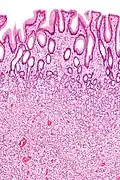

| Juvenile Polyp | Upper GI tract and colon | Cystically dilated glands with expanded lamina propria | Not inherently, may develop dysplasia | ![]() |

Juvenile polyposis syndrome, identical polyps in Cronkhite–Canada syndrome |